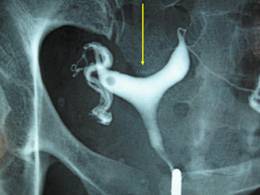

L’Hystérosalpingographie permet de juger de la perméabilité tubaire à la recherche d’une sténose, d’une obstruction ou de diverticules évoquant ou encore, une mauvaise diffusion du produit de contraste traduisant l’existence d’adhérences pelviennes. Elle peut aussi montrer des anomalies endocavitaires: synéchie, myome sous muqueux ou polype, adénomyose.